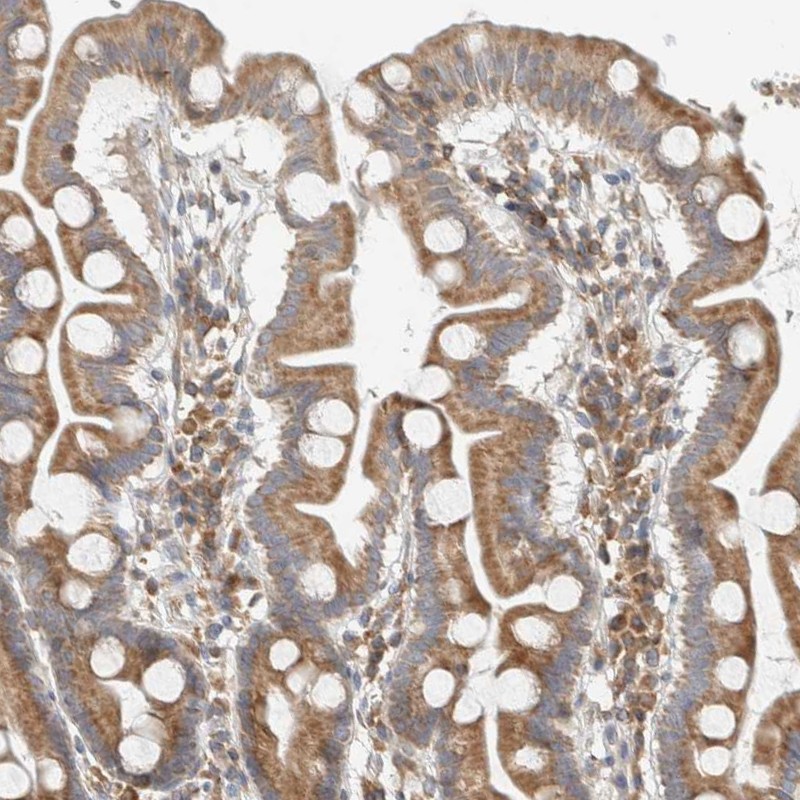

Immunohistochemical staining of human duodenum shows moderate cytoplasmic positivity in glandular cells.